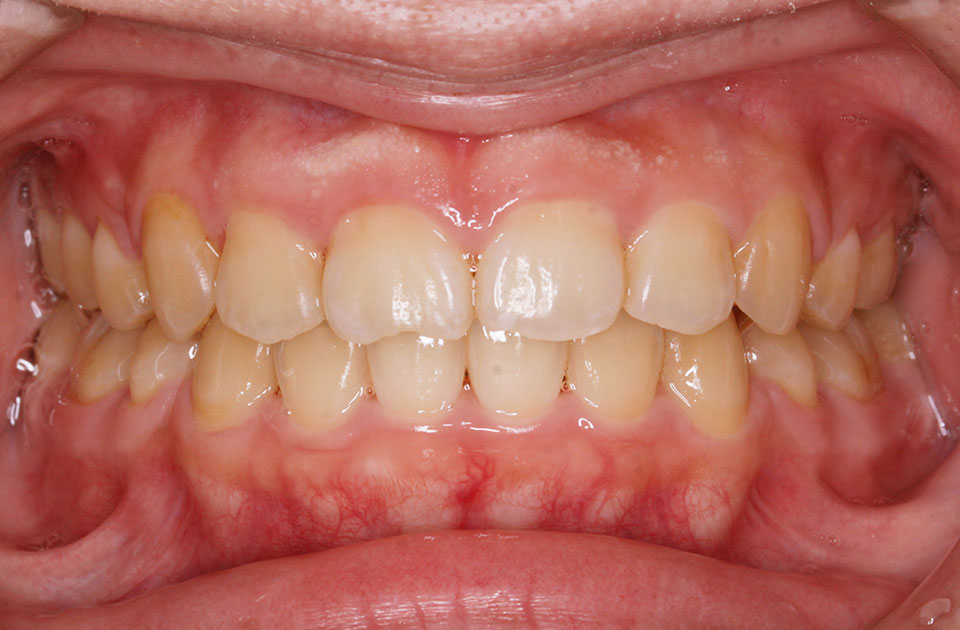

矯正後 正面

矯正前 正面